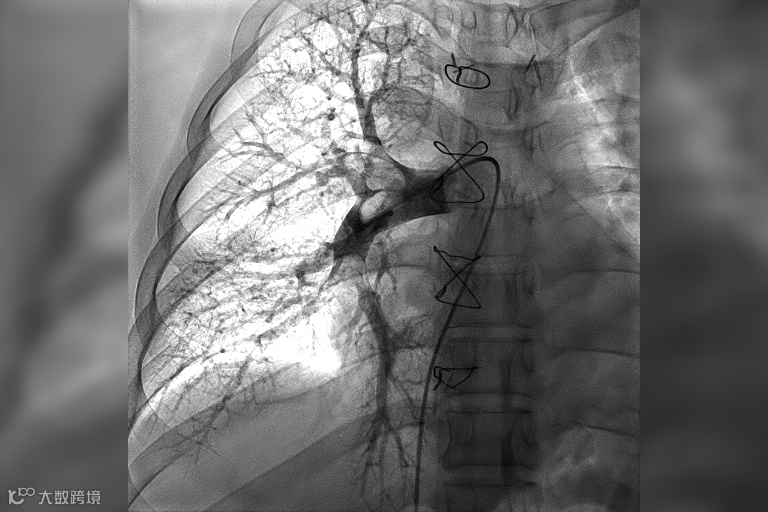

术前肺动脉造影术提示右肺动脉大面积血栓

时间就是生命。在我院快速急诊手术准备后,心内科副主任医师王承带着团队进入导管室。只见医生操作娴熟,选用新型取栓支架,灵活地经导管,一条一条地取出大量暗红色血栓。小章即刻感觉呼吸通畅,氧饱和度上升至95%以上。术后复查肺动脉造影术提示他的右肺动脉血栓影已完全消失,肺动脉血流通畅,各项血流动力学指标也明显改善。整台介入手术用时仅用30分钟,就立竿见影地让患者转危为安。